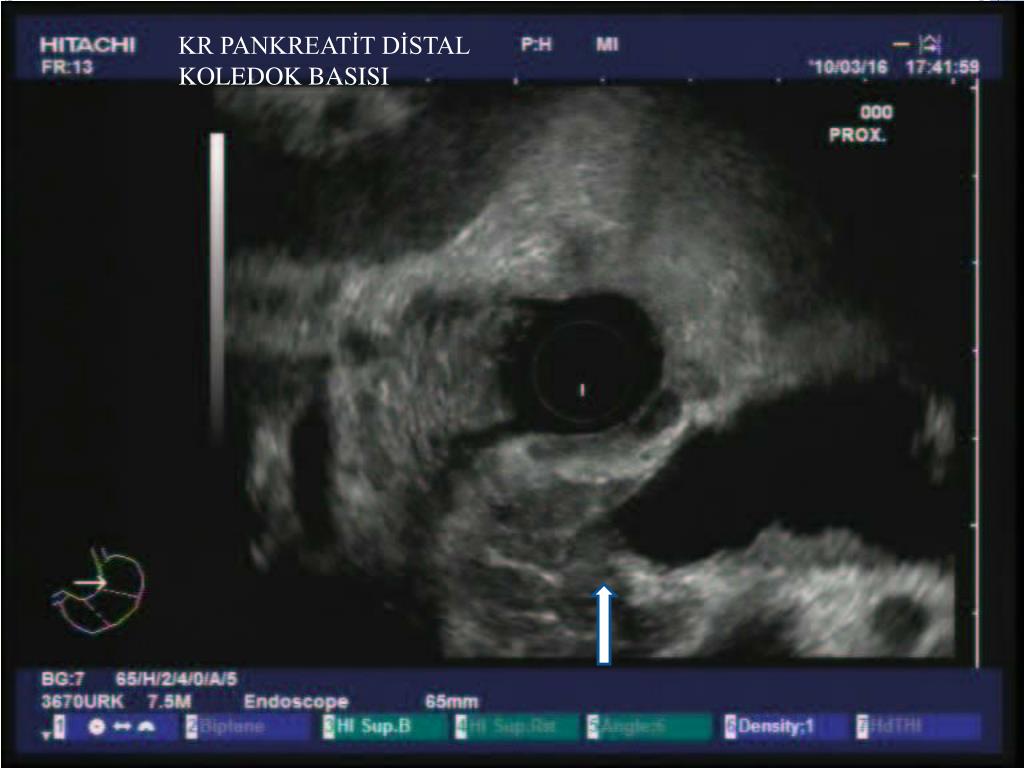

22. KR PANKREATİT DİSTAL KOLEDOK BASISI